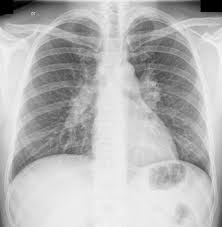

χρόνια σαρκοείδωση. Η χρόνια μορφή σαρκοειδώσεως ακολουθεί μια περισσότερο ήπια διαδρομή και συχνά αναγνωρίζεται σε σχετικά μεγαλύτερες ηλικίες κι επινεμείται περισσότερους ιστούς (εικόνα παραπάνω).

-χρόνια πνευμονική σαρκοείδωση. Επινεμείται το πνευμονικό παρέγυχμα, όπως αναγνωρίζεται η δικτυακή μεταβολή του, στις απεικονιστικές εξετάσεις, ιδίως στα περιπυλαία πνευμονικά πεδία. Από τη φυσική εξέταση, συνήθως αναγνωρίζεται περιορισμένος αριθμός ευρημάτων, ενώ η πνευμονική λετορυγία μπροεί αν διατηρείται σε αποδεκτά όρια. Από τη σπιρομέτρηση αναγνωρίζονται μικτού τύπου μείωση τηςε ικανότητας αερισμού (δδ από καρδιακή ανεπάρκεια). Σε μικρότερο αριθμό ασθενών η σαρκοείδωση μπορεί να μεταπέσει βαθμιαίως σε πνευμονική ίνωση και απώλεια πνευμονικής λειτουργίας, με διαταραχή στην ικανότητα διαχύσεως αερίων, μείωση τνω πνευμονικών όγκων, κια αρχικά, αποφρακτικού τύπου μείωση της ικανότητας αερισμου΄(λόγω της ενδοβρογχικής αναπτύξεως κοκκιωμάτων. Αναγνωρίζεται απόφραξη των μικρών αεραγωγών, παγίδευση αέρος και σχηματισμός φυσαλίδων.